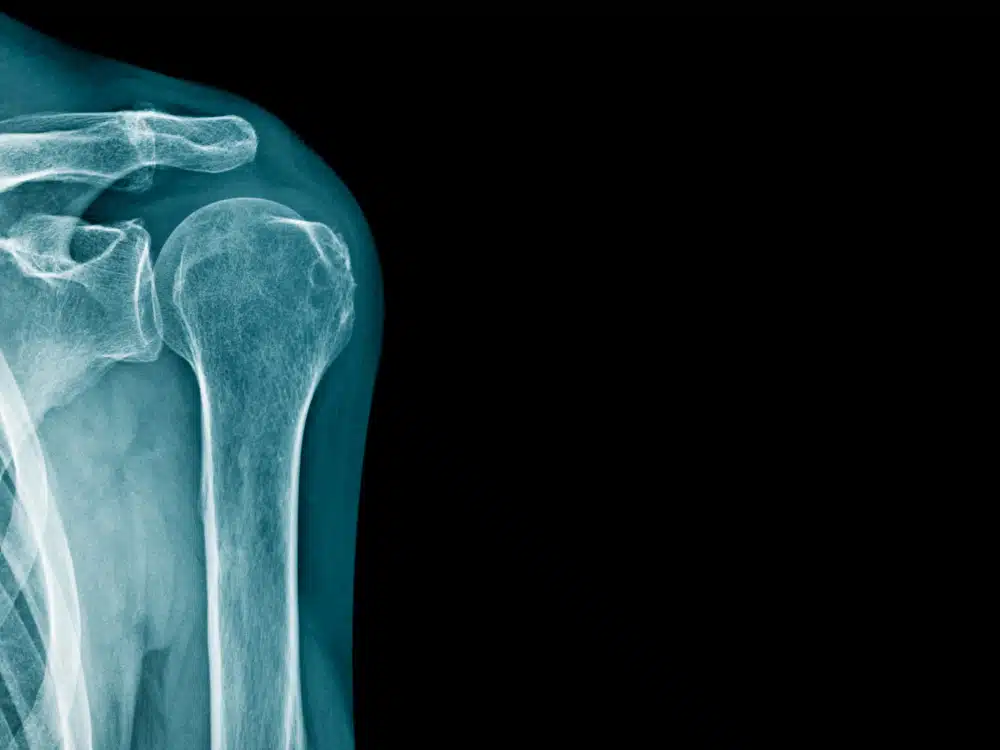

Bewegungstherapie wirkt bei Frozen Shoulder

Eine Übersichtsstudie zeigt: Wenn das Schultergelenk „einfriert“ wirken Übungen am besten.